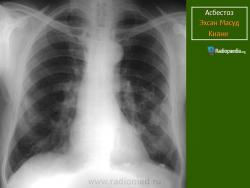

Асбест 2 ПА

Дата: 06/02/2004

Просмотров: 582